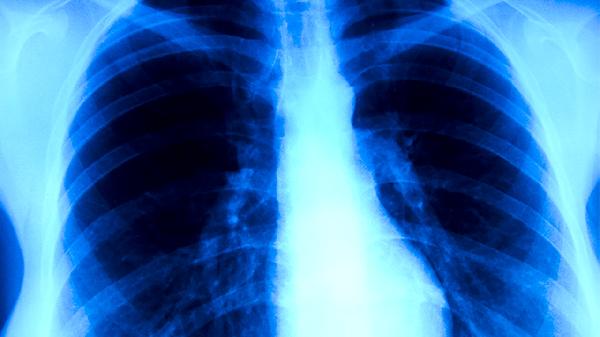

肺结核患者经规范抗结核治疗后,痰涂片检查连续多次阴性可判定为无传染性,但病灶中仍可能存在处于休眠状态的结核菌。此时若擅自停药,残留细菌可能重新活跃导致病情反复,甚至发展为耐多药结核病。标准短程化疗方案通常需6-9个月,强化期使用异烟肼片、利福平胶囊、吡嗪酰胺片、乙胺丁醇片四联用药,巩固期减少为异烟肼片和利福平胶囊。治疗期间需定期复查胸部CT和痰培养,由医生评估是否调整用药。部分患者病灶吸收缓慢或存在肺外结核,可能需要延长疗程至12个月。